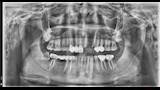

وأشار إسلام إلى أن معاناته بدأت بعد العملية مباشرة، إذ لم تلتئم اللثة رغم مرور ستة أشهر، وبدأ يشعر بإعياء ومشكلات دفعته للتوجه إلى طبيب آخر، والذي طلب منه إجراء أشعة مقطعية وأشعة بانوراما. وقال إنه فوجئ بتشخيص الطبيب بوجود تآكل شديد بعظام الفك العلوي في مواضع الزرع، ووجود خُراجين صديديين، بالإضافة إلى استقرار أحد مسامير الزرعات داخل الجيب الأنفي، وعدم ثبات الزرعات في مكانها.

وأوضح أن عدة أطباء أكدوا له أن هذه المضاعفات نتجت عن العملية، وأن الطبيب الذي أجرى الزراعة لم يطلب أي فحوصات أو إشعات قبلية، مشيرًا إلى أن بعض الأطباء رفضوا كتابة تقارير طبية بالحالة “حتى لا يضعوا أنفسهم في موقف محرج مع الزملاء”.